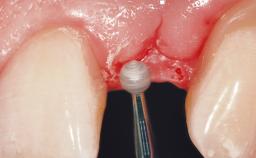

Immediate Placement of an Implant in a Maxillary Left Central Incisor Site

| Soft Tissue Grafting | Simultaneous |

| Placement Protocol | Immediate implant placement |

| Tooth Site | Maxillary incisor or canine |